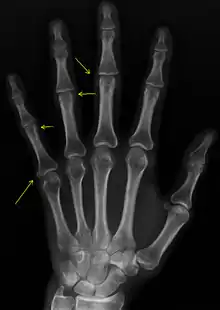

| CREST syndrome (calcinosis and sclerodactyly) | |

CREST causes thickening and tightening of the skin with deposition of calcific nodules ("calcinosis").

Sclerodactyly

Though it is the most easily recognizable manifestation, it is not prominent in all patients. Thickening generally only involves the skin of the fingers distal to the metacarpophalangeal joints in CREST. Early in the course of the disease, the skin may appear edematous and inflamed. Eventually, dermal fibroblasts overproduce extracellular matrix leading to increased tissue collagen deposition in the skin. Collagen cross-linking then causes a progressive skin tightening. Digital ischemic ulcers commonly form on the distal fingers in 30-50% of patients.[3]